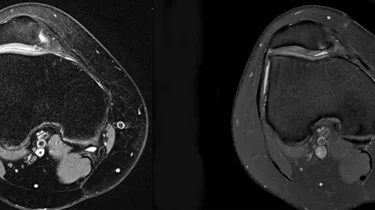

Ortopædkirurgi Lars Blønd har for nyligt udviklet en ny og vellykket operationsteknik til behandling af Artroscopisk Trokleoplastik, der udføres med en kikkertoperation.